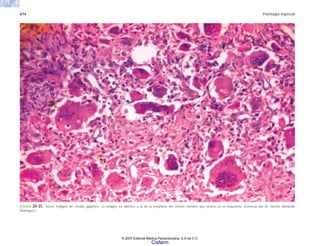

FIGURA 6-31. a) Vasculitis coronaria en un caso de SIDA que muestra necrosis